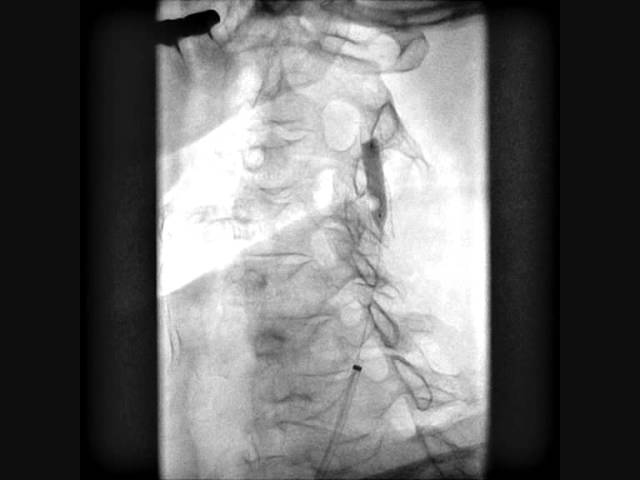

Хирургическая процедура обычно осуществляется под действием местного наркоза и под контролем специального оборудования, которая контролирует количество сердечных сокращений и уровень артериального давления во время операции. Для того чтобы контролировать самочувствие пациента и функцию его головного мозга, врач разговаривает с ним и просит систематически сжимать, находящуюся в руке игрушку и маленький мяч. Некоторые специалисты предпочитают производить стентирование сосудов под общим наркозом. Перед началом непосредственно самой операции, больному в вену вводится раствор гепарина, это делается с целью уменьшения свертываемости крови.

Затем в крупный сосуд руки или ноги вводится специальный катетер, на его кончике находится надувающийся баллончик. Этот катер подводится к месту патологического процесса, надувается и тем самым расширяет просвет сосуда. Стоит отметить, что весь процесс контролируется на специальном рентген аппарате.

После того как просвет сосуда был расширен при помощи баллончика, осуществляется установка стента, который вводится к пораженному участку при помощи другого катетера. Как только цилиндрическая конструкция оказывается в нужном участке, она расправляется и вживляется в стенку. Затем катетеры и фильтр устраняются, а стент остается на положенном месте. Обычно длительность операции не превышает одного — двух часов, но бывают и исключения, когда процедура затягивается на более продолжительное время.